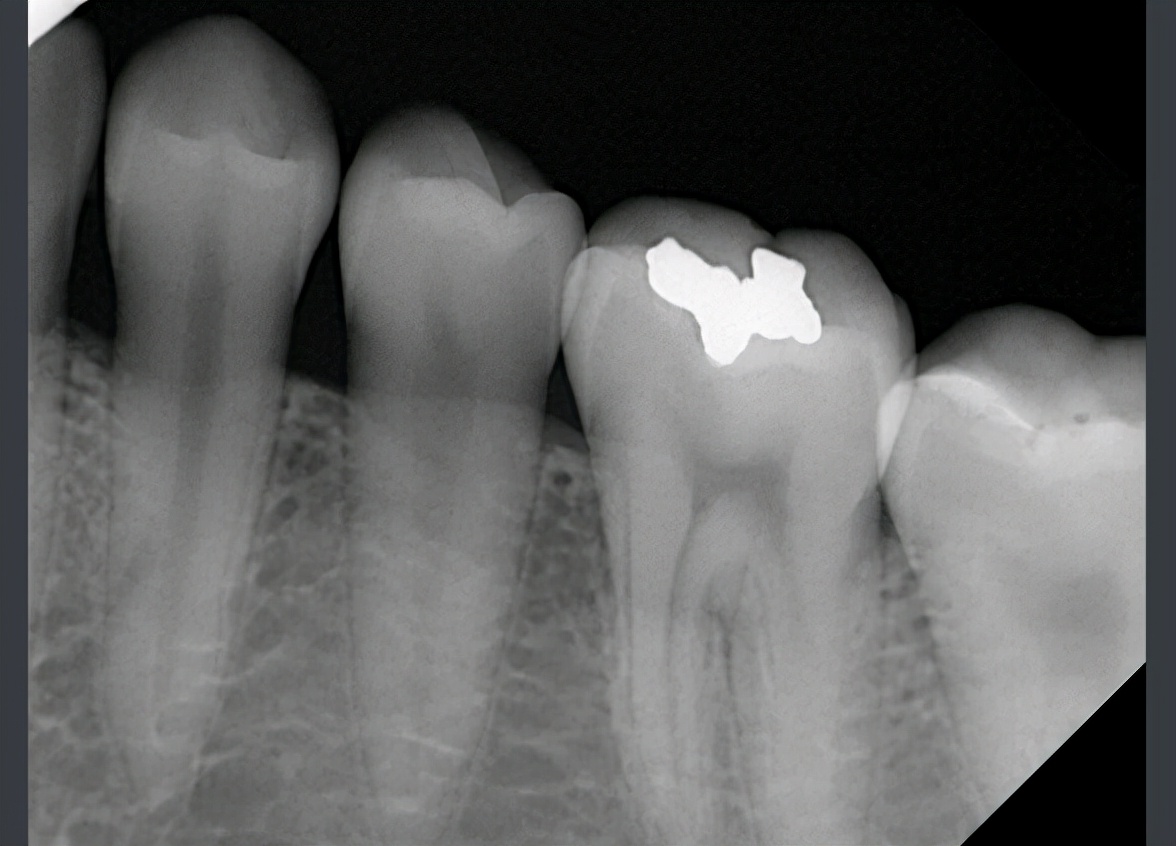

全新口内传感器,适用于牙科诊所、口腔门诊以及宠物医院。宠物用X射线拍摄。